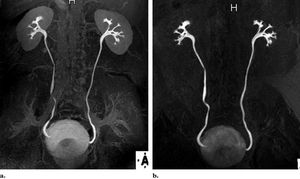

(a) On a coronal MIP image from excretory MR urographic data obtained with a 3D interpolated fat-suppressed gradient-echo sequence (VIBE/THRIVE/LAVA) during breath holding, soft-tissue suppression is minimized owing to the use of a relatively low flip angle of 12°. (b) Coronal MIP image from excretory MR urographic data obtained with a 3D gradient-echo MR angiographic sequence shows improved background tissue suppression due in part to the use of a higher flip angle of 40° (Leyendecker et al 2008)